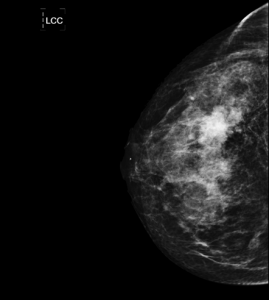

JUSTIFICACIÓN: La respuesta correcta es b) Mamografía. La Mamografía es la prueba de elección en el estudio de la mama ante una exploración positiva y el primero en el cribado de pacientes con edad superior a 35 años. Esto es así por sus elevadas sensibilidad y especificidad.